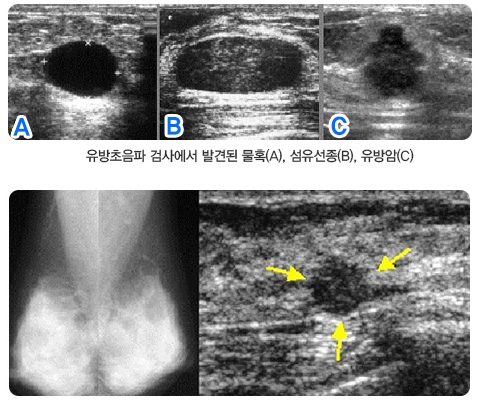

유방초음파검사에서 발견된 물혹, 섬유연종, 유방암

여자 40세, 정기 검진을 위하여 내원

유방촬영술(좌측)에서 양측유방은 치밀유방이었으며 유방암의 소견은 없었다. 그러나 동시에 시행한 초음파검사(우측)에서 5mm크기의 유방암(화살표)을 발견하였다. 이와 같이 치밀유방에서는 유방촬영술의 예민도가 감소한다. 이러한 경우 유방촬영술의 보조적인 검사로 유방초음파를 병행하면 유방암의 발견율을 높일 수 있다.